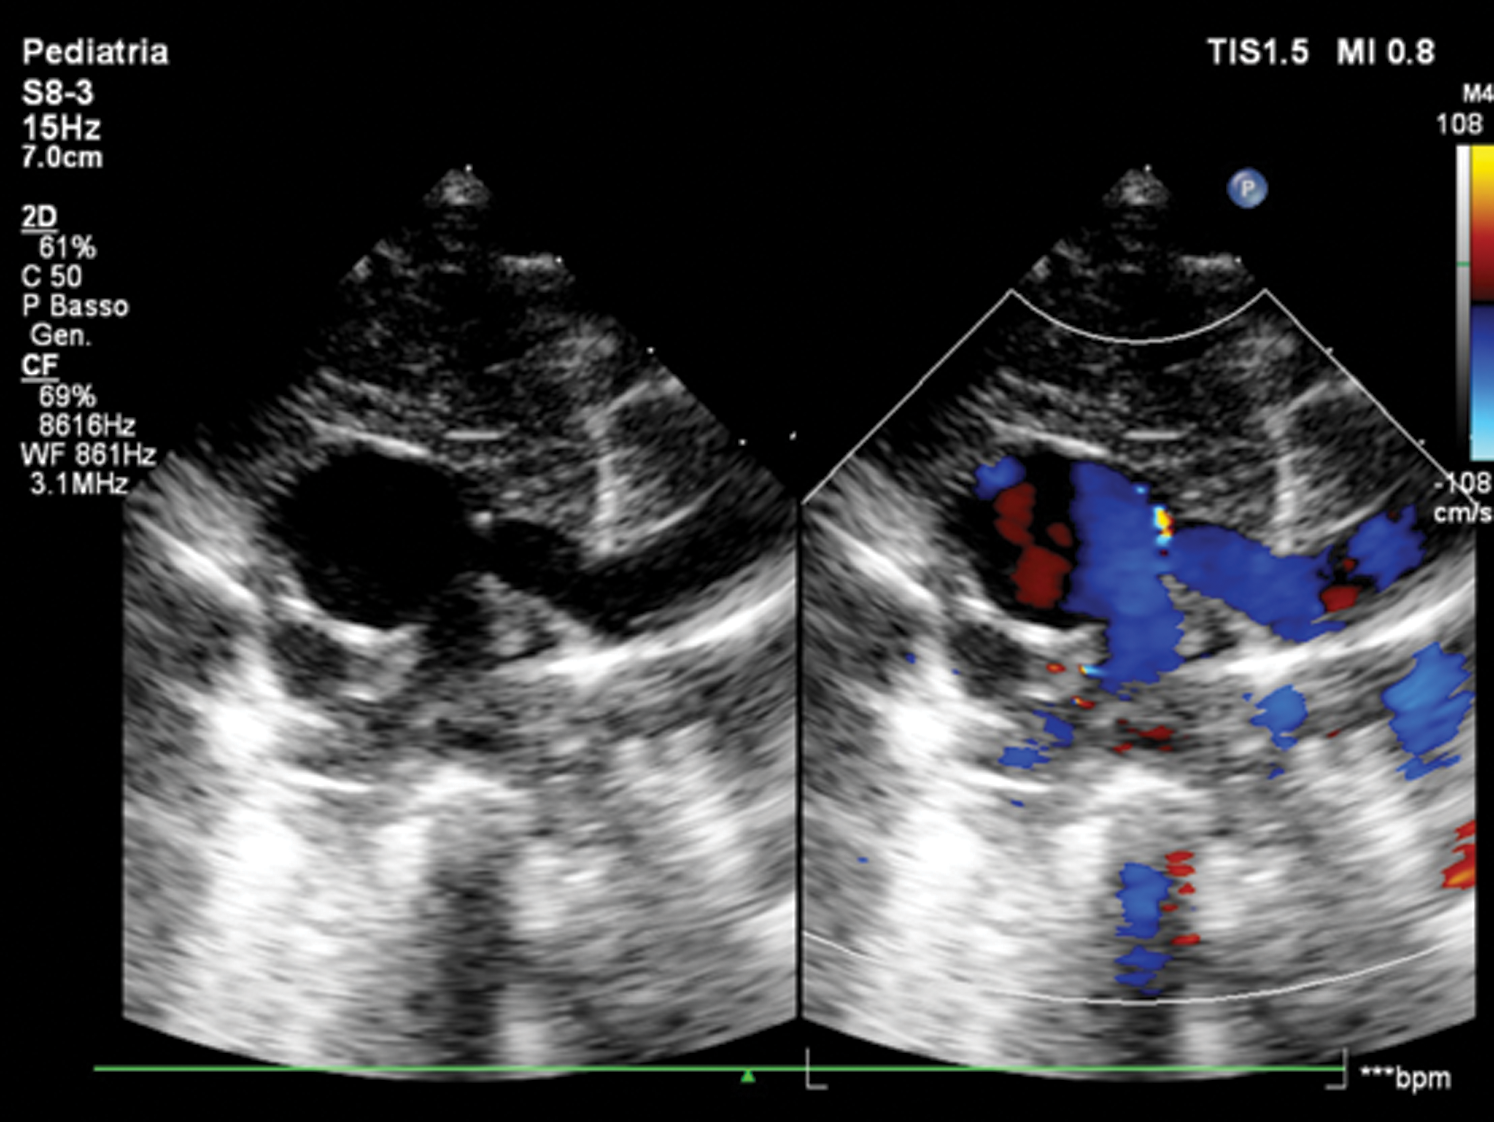

Echocardiogram showed CAT Type II CE (Fig. 1), a quadricuspid truncal valve (Figs. 2A and 2B) with moderate stenosis (Gmax 40 mmHg), reversal flow in descending aorta due to significant truncal valve regurgitation, and ventricular septal defect of 8 mm shunting left-to-right. Single coronary ostium was detected at 10 o’ clock in short axis view.

Figure 1: Short-axis view of common arterial trunk Type 2 CE